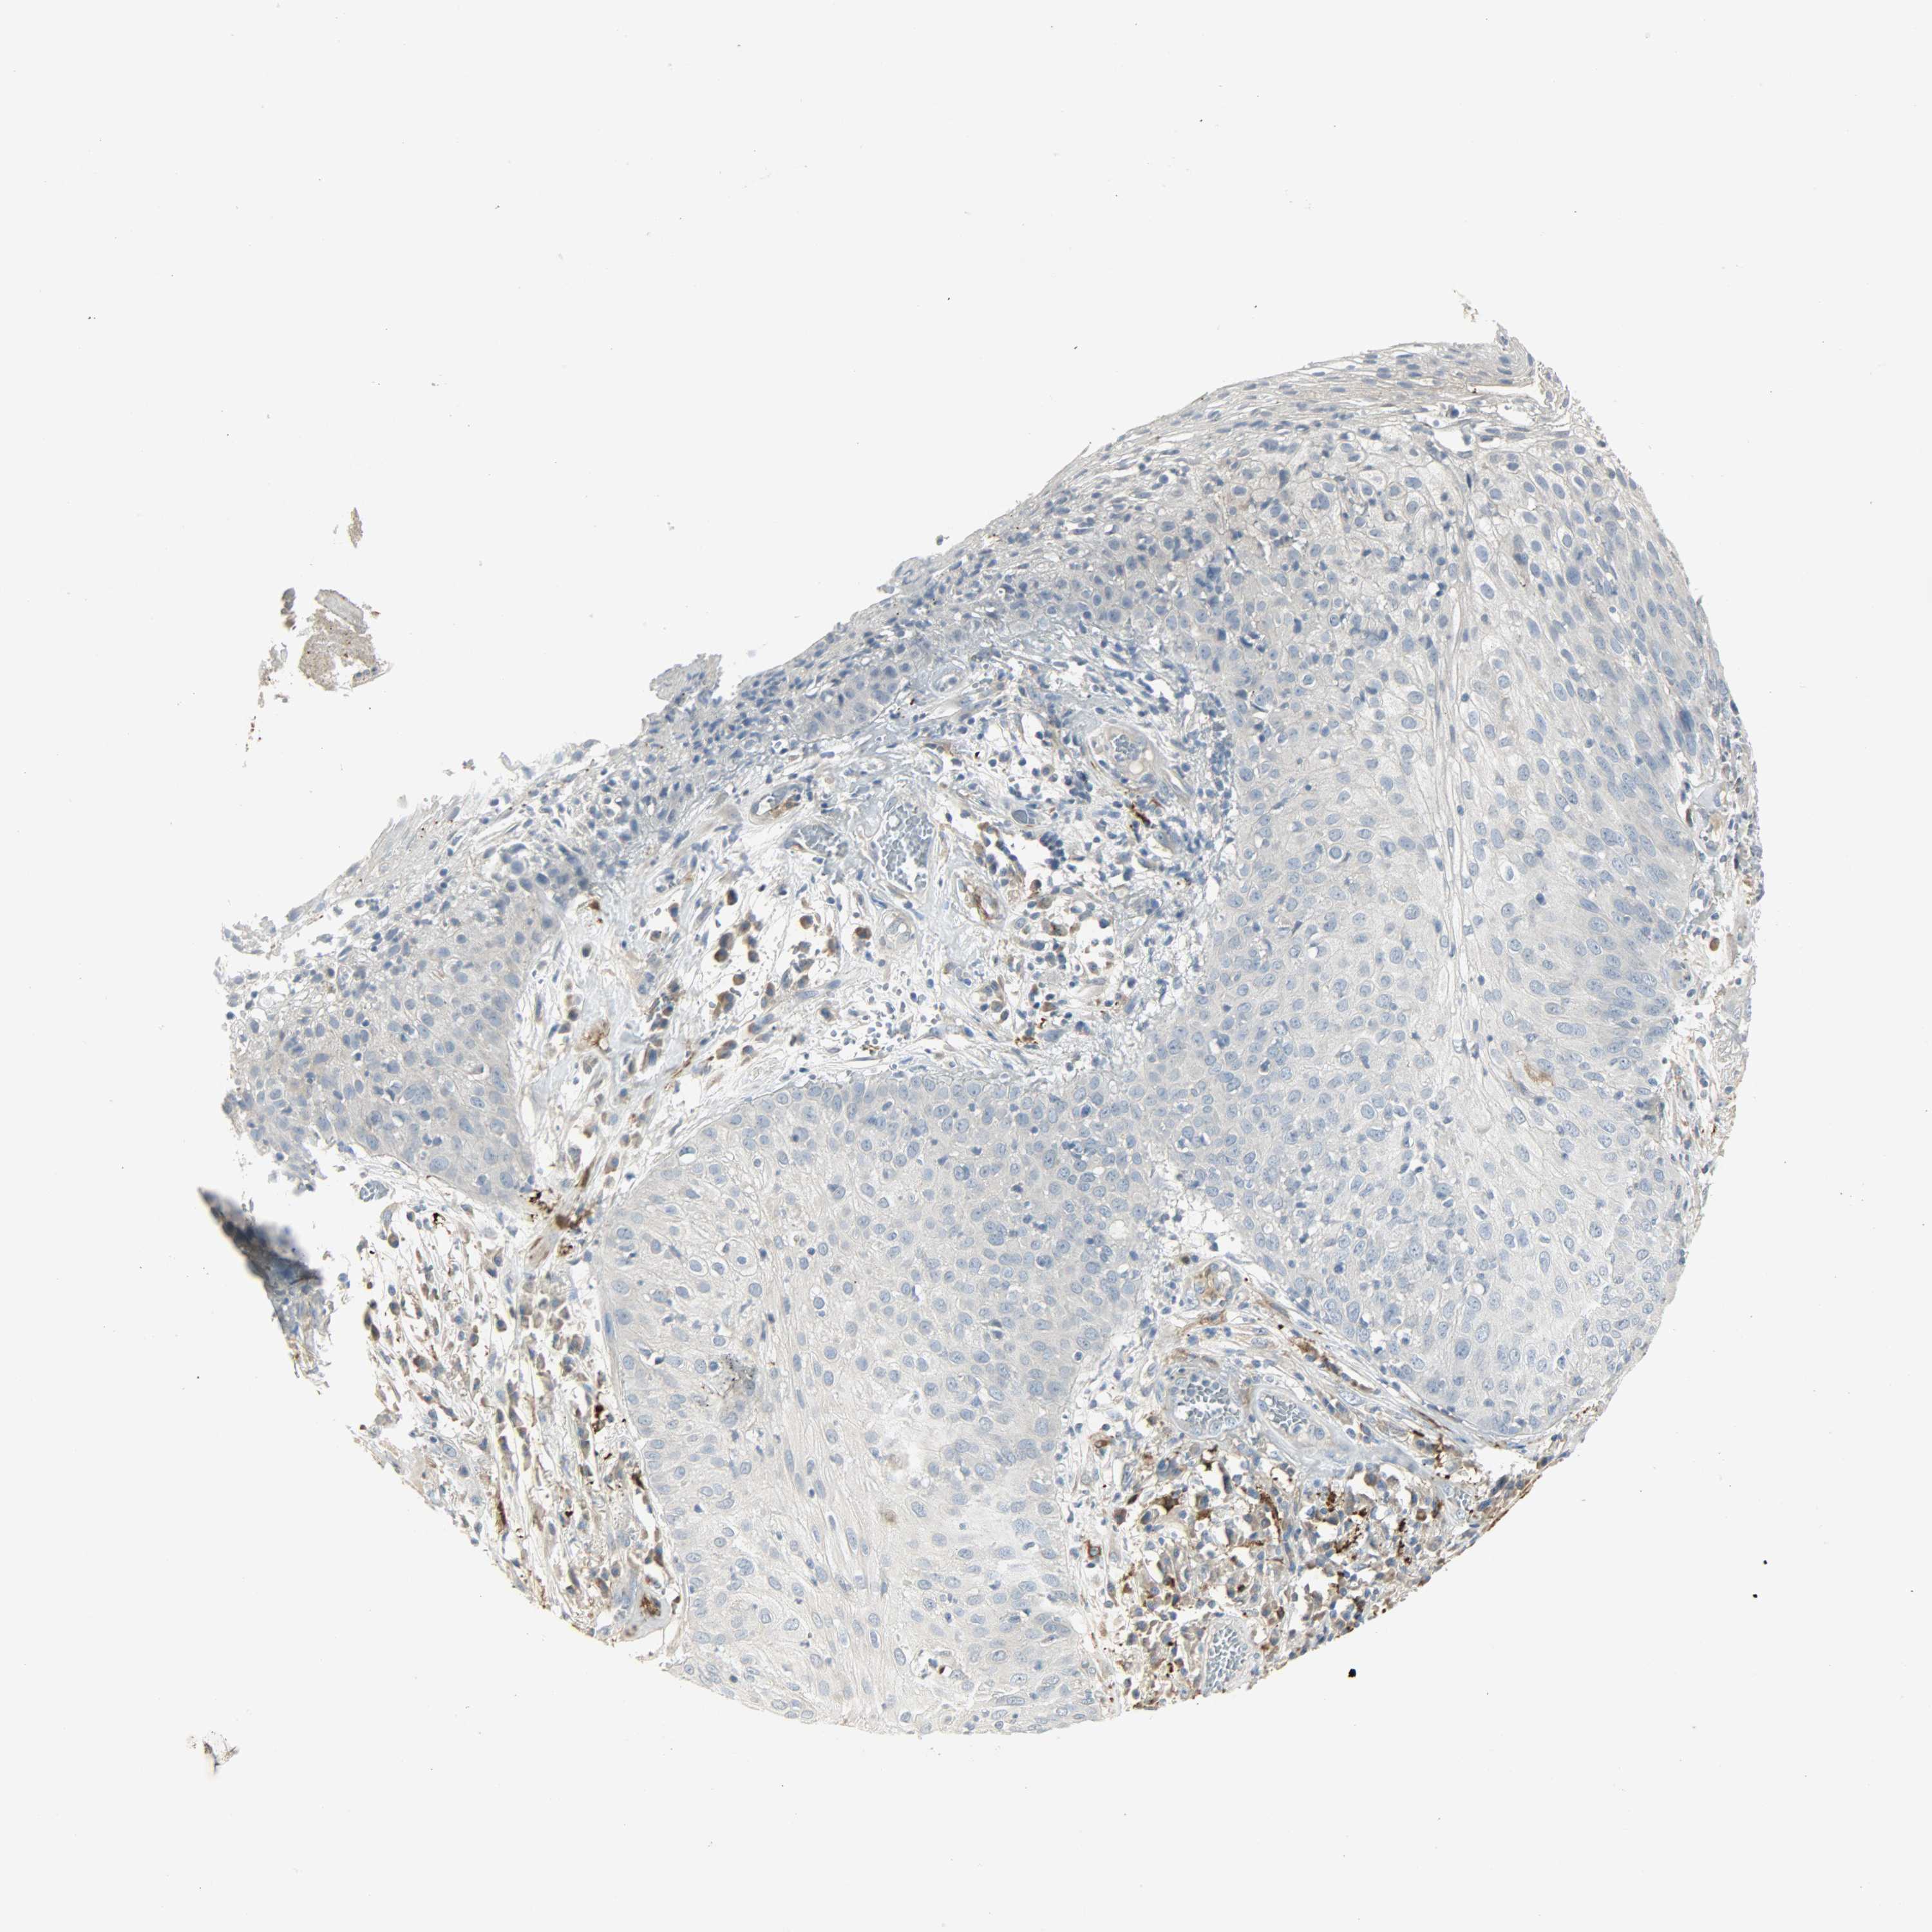

SKIN CANCER - Protein expressioni

A mouse-over function shows sample information and annotation data. Click on an image to view it in a full screen mode. Samples can be filtered based on level of antibody staining by selecting one or several of the following categories: high, medium, low and not detected. The assay and annotation is described here.

Each image is clickable and will lead to virtual microscopy that enables deeper exploration of all samples and also displays staining intensity scores, fraction scores and subcellular localization as well as patient and tissue information for each sample.

Antibody HPA005128

Squamous cell carcinoma, NOS

Basal cell carcinoma